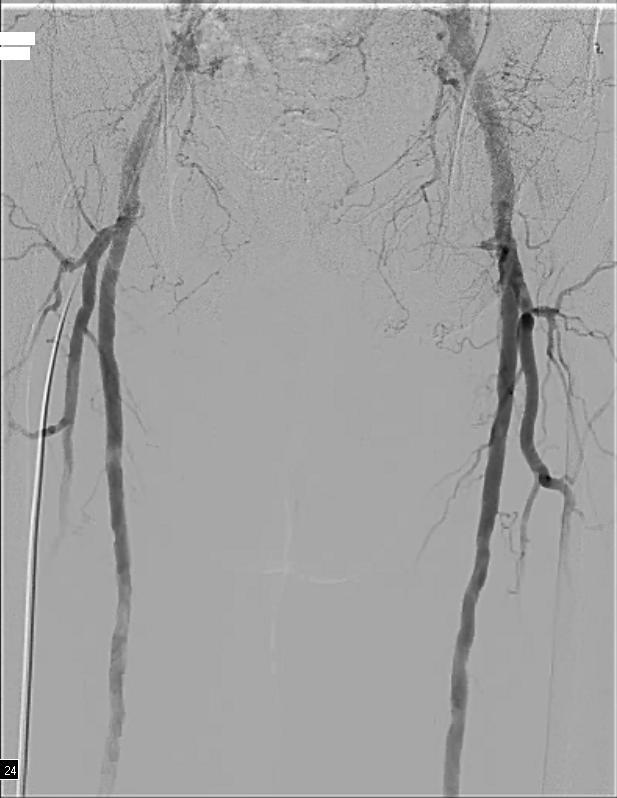

Angiography revealed bilateral occlusions of the anterior and posterior tibial arteries. Iliac and femoral arteries were free of significant disease (Figure 1):

There was a severe stenosis of the left tibioperoneal trunk (Figure 2) and single vessel runoff to the foot via the left peroneal artery (Figure 3):

Angioplasty of the left tibial arteries was performed for limb salvage. With support from a 6F 65 cm sheath via the right common femoral artery, a 3×20 mm balloon was used for angioplasty of the left tibioperoneal trunk. A 0.018 inch Confianza Pro 12 wire (Abbott Vascular, Abbott Park, IL) and support catheter was used to cross the occluded anterior tibial artery, which was then angioplastied with multiple inflations of a 3×100 mm balloon, producing a good result (Figure 4):